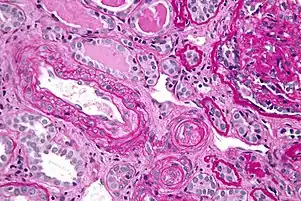

Micrograph showing thrombotic microangiopathy, the histomorphologic finding seen in scleroderma renal crisis, kidney biopsy, PAS stain

Kidney involvement, in scleroderma, is considered a poor prognostic factor and frequently a cause of death.[13]

The most important clinical complication of scleroderma involving the kidney is scleroderma renal crisis (SRC), the symptoms of which are malignant hypertension (high blood pressure with evidence of acute organ damage), hyperreninemia (high renin levels), azotemia (kidney failure with accumulation of waste products in the blood), and microangiopathic hemolytic anemia (destruction of red blood cells).[14] Apart from the high blood pressure, hematuria (blood in the urine) and proteinuria (protein loss in the urine) may be indicative of SRC.[15]

In the past, SRC was almost uniformly fatal.[16] While outcomes have improved significantly with the use of ACE inhibitors,[17][18] the prognosis is often guarded, as a significant number of patients are refractory to treatment and develop kidney failure. About 7–9% of all diffuse cutaneous scleroderma patients develop renal crisis at some point in the course of their disease.[19][20] Patients who have rapid skin involvement have the highest risk of renal complications.[21] It is most common in diffuse cutaneous scleroderma, and is often associated with antibodies against RNA polymerase (in 59% of cases). Many proceed to dialysis, although this can be stopped within three years in about a third of cases. Higher age and (paradoxically) a lower blood pressure at presentation make dialysis more likely to be needed.[22]